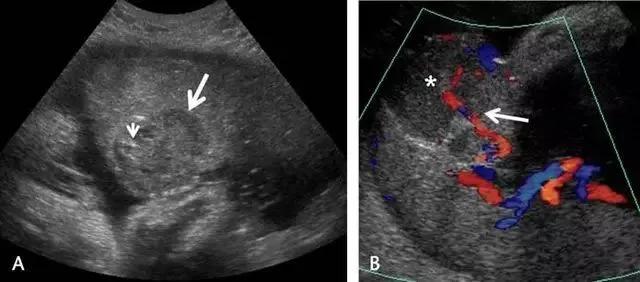

葡萄胎可分化为侵袭性葡萄胎及胎盘位置的滋养细胞肿瘤或绒癌。侵袭性葡萄胎的特点是滋养层的过度生长,并子宫肌层的广泛深度渗入;这种侵袭过程为局部性的,并未发生转移,与绒癌不同。在超声上,侵袭性葡萄胎的包块为高速、低阻性血流,其阻力指数尚低于完全性葡萄胎的阻力指数(图 18)。

图 18 为侵袭性葡萄胎:孕妇 35 岁,曾患完全性葡萄胎、并接受清宫,现在 HCG 持续升高。此图示宫腔扩张,内充满不均质的软组织,血流丰富,内膜与肌层的界限消失(箭头)。超声还可见较大的多房性卵巢囊肿(黄素囊肿,此图未显示)

胎盘绒毛膜血管瘤是一种少见的具有胎儿血供的良性肿瘤,多位于胎盘的子面,居脐带进入胎盘处附近,可随着孕龄增加而增大。大于 5 cm 时,可导致羊水过多或过少、出血、早产、胎盘早剥、前置胎盘,胎儿非免疫性水肿,甚至胎儿窘迫或死亡,因而应经常对其进行超声随访。其表现是边界清晰的低回声包块,突出于胎盘表面,可能伴有钙化,表明瘤内血供减少及预后较好。瘤内如果测及高速动脉血流,则预示可能出现胎儿水肿(图 19)。

图 19 示胎盘绒毛膜血管瘤:A 为孕 35 周的胎盘绒毛膜板附近的低回声包块(长箭头),内见微小钙化(短箭头)。B 为 A 的彩色血流图,可见一支血管向肿块供血(箭头),星号指示肿块内的血供情况。孕妇无异常表现,足月生产一正常胎儿,胎盘的组织学检查证实为绒毛膜血管瘤